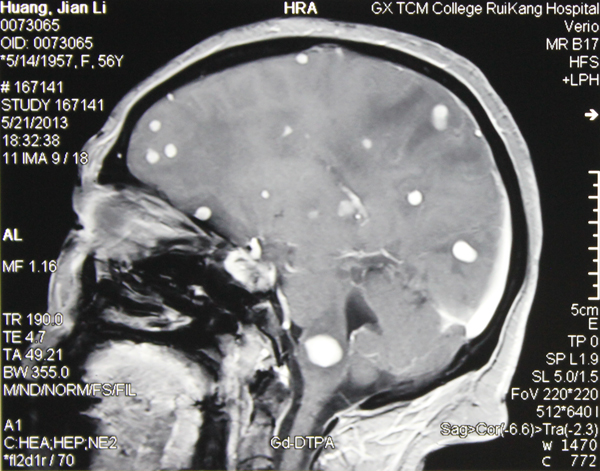

对于桌面上近一尺厚从各家医院带来的检查报告单和影像胶片,朱医生直言:整整花了一个下午才看完。从脑部CT片上可以看到黄阿姨的大脑星罗棋布地分布着点点白斑,盛医生说,各种报告都提示脑部存在病变,却不能明确病变性质。

眼看着阿姨的病情愈加严重,神经外科发挥集体的力量,多次讨论,翻阅大量资料,最终认定黄阿姨脑部患上了炎症疾病,极有可能是真菌感染,那些白斑和白点就是感染的部位。

抗真菌感染治疗前,黄阿姨脑部布满点点真菌